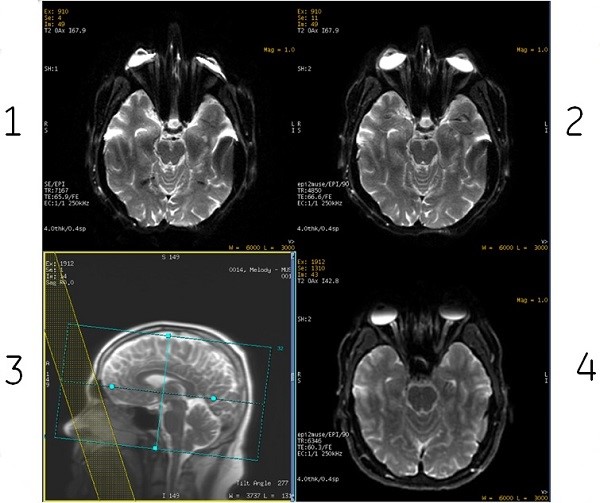

- The inherent susceptibility-induced geometric distortions in EPI-based DWI and DTI scans can be reduced by applying ASSET Imaging Option. ASSET requires a calibration scan and a mismatch between the calibration scan (RF sensitivity profile) and the EPI-based DWI/DTI scan due to susceptibility effects and motion might result in aliasing of bright structures such as eyeballs in T2 (b=0) and/or lower b-value images [1], see the following image. In the case of MUSE, potential shot-to-shot mismatch due to motion/inherent phase errors coupled with higher resolution images might exacerbate the problem such that aliasing artifacts from bright structures (e.g eyeballs) could be seen more frequently [2]. It is also important to note that derived images such as ADC and FA maps will also show this artifact if it is visible on lower b-value and/or T2 (b=0) images.

SAT band placement over the eyeballs was reported in literature as an effective way to mitigate eyeball aliasing [1]. Care should be taken to avoid inadvertent suppression of signals from the region of interest.

Figure 4. Eyeball artifact

Table 2. Image legend Number Description 1 Example of eyeball ghosting in a single-shot EPI scan. 2 Example of eyeball ghosting in a multi-shot-EPI scan. 3 SAT band placement over eyeballs mitigates the eyeball artifact. 4 Mitigated the eyeball artifact from SAT band. [1] Chou, M-C., et al. "Pseudolesions arising from unfolding artifacts in diffusion imaging with use of parallel acquisition: origin and remedies." American journal of neuroradiology 28.6 (2007): 1099-1101.